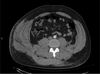

A 65-year-old man comes to the office because of an infected wound to the left plantar region. Medical history includes type 2 diabetes mellitus. Dorsalis pedis and posterior tibial pulses are not palpable but are located with a handheld Doppler probe. Ankle brachial index cannot be obtained because of noncompressible vessels in the left lower extremity, below the knee. Which of the following is the most appropriate next step in evaluating the arterial perfusion of this patient’s foot?

The correct response is Option E.

The most appropriate next step when evaluating the arterial perfusion of this diabetic patient’s foot is obtaining a toe-brachial index (TBI). TBI is calculated by dividing the great toe systolic pressure by the brachial systolic pressure. An index of >0.7 is considered normal.

Patients with diabetes mellitus have a higher incidence of peripheral arterial disease than the non-diabetic population. Atherosclerotic lesions in diabetic patients tend to favor the arteries below the knee, which also commonly display medial calcinosis, causing stiffening of the arterial walls, poor compressibility, and an unreliably high ankle-brachial index (ABI). Interestingly, the small vessels of the great toes are usually spared of disease, therefore the diagnostic advantage of TBIs. These features should be taken into consideration whenever assessing arterial blood flow to the distal lower extremity of a diabetic patient.

Percutaneous arteriography is an invasive procedure and should be reserved for when surgical or endovascular therapeutic interventions are anticipated. Computed tomography arteriography and magnetic resonance arteriography may also be used in the diagnosis of peripheral artery disease in the lower extremities, but a normal TBI would most likely preclude their need. Repeating the ABI would most likely render a similar result, as the inability to compress the arteries in the leg is due to stiffened vessel walls.